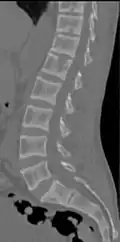

X-ray of a subtle "rugger jersey spine" due to sclerotic bands adjacent to the vertebral endplates.[18] -

CT scan of the same case.[18]

Renal osteodystrophy is usually diagnosed after treatment for end-stage kidney disease begins; however the CKD-MBD starts early in the course of CKD.[1][6] In advanced stages, blood tests will indicate decreased calcium and calcitriol (vitamin D) and increased phosphate, and parathyroid hormone levels. In earlier stages, serum calcium, phosphate levels are normal at the expense of high parathyroid hormone and fibroblast growth factor-23 levels. X-rays will also show bone features of renal osteodystrophy (subperiostic bone resorption, chondrocalcinosis at the knees and pubic symphysis, osteopenia and bone fractures) but may be difficult to differentiate from other conditions. Since the diagnosis of these bone abnormalities cannot be obtained correctly by clinical, biochemical, and imaging methods (including measurement of bone-mineral density), bone biopsy has been, and still remains, the gold standard analysis for assessing the exact type of renal osteodystrophy.[6][16]